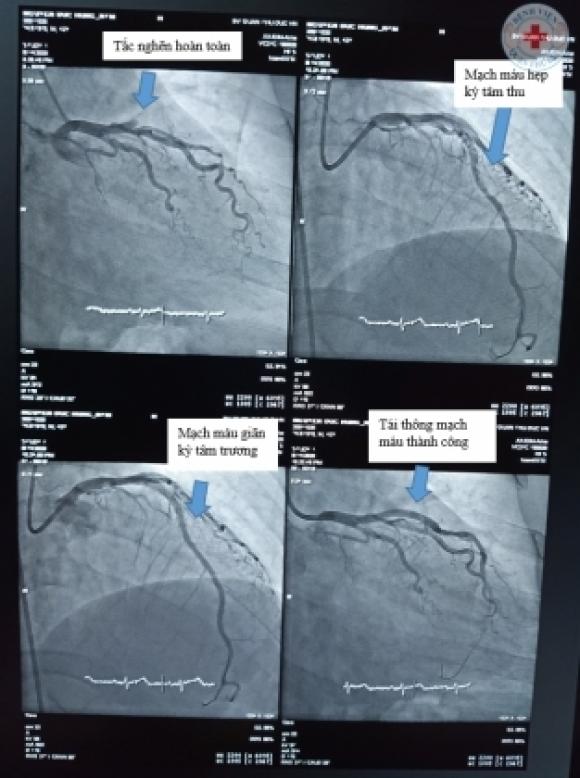

Bệnh nhân xét nghiệm men tim tăng cao. Kết quả siêu âm tim phát hiện thành trước tim giảm co bóp nặng, chức năng tim giảm 30-35%. Sau khi chụp mạch vành qua da, bệnh nhân được xác thực chẩn đoán: tắc hoàn toàn động mạch liên thất trước trái ngay từ sau lỗ vào.

Ngay lập tức, bệnh nhân đã được các bác sĩ can thiệp hút huyết khối lớn, có nhiều mảng huyết khối dài. Đồng thời, kíp can thiệp cũng đặt thành công 01 stent phủ thuốc để tái tạo mạch máu chỗ hẹp. Sau can thiệp cho thấy mạch máu thông tốt sau thủ thuật, dòng chảy bình thường, ngay sau chỗ tắc hẹp có tình trạng cầu cơ động mạch vành gây hẹp 30% mạch máu.

Hình ảnh trên phim chụp của bệnh nhân